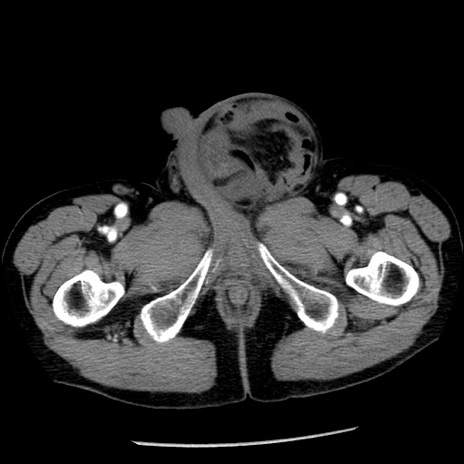

症例26(横断像)

【症例】80歳代男性

【主訴】嘔吐

【現病歴】昨晩2回嘔吐あり、今朝になっても嘔吐あり。来院。

【既往歴】胃潰瘍

【身体所見】意識清明、BT 37.6℃、BP 166/95mmHg、HR 100bpm、SpO2 97%、腹部:平坦・軟、腸蠕動音聴取良好、圧痛なし。

【データ】WBC 21900、CRP 1.46